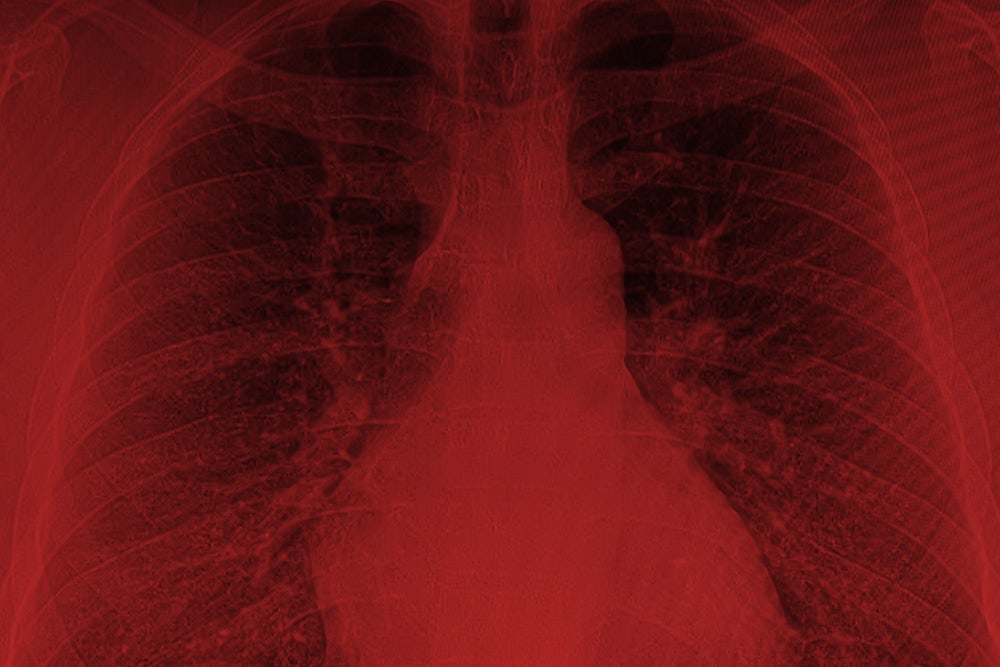

It didn’t take long for soldiers to begin to fall ill. As early as 2004, veterans who had served near burn pits began complaining of a complex and enigmatic constellation of symptoms: asthma, sinusitis, bronchitis, unexplained diarrhea, persistent runny nose or cough, severe headaches and abdominal pain, ulcers, weeping lesions on the extremities, chronic infections. Many coughed up black mucus, which they called “plume crud,” “black goop,” or “Iraqi crud.” Some developed cancers—tumors grew on their lungs, brains, bone, and skin—including leukemia. Others suffered from severe respiratory conditions, including chronic obstructive pulmonary disease and constrictive bronchiolitis, a rare and often fatal lung disorder for which there is no treatment.

Finally, a doctor at National Jewish Health in Denver referred him to Robert Miller, a pulmonary specialist at Vanderbilt University who had conducted a study on veterans from Iraq and Afghanistan with post-deployment respiratory problems. Like Baca, many of the soldiers had been exposed to the burn pits. When Miller did biopsies on the vets, he found that a high percentage of them had constrictive bronchiolitis, an incurable and often terminal illness. “It’s an untreatable disease,” Miller said at the time. “We don’t know what’s going to happen to these people down the road.”

In 2009, Jessey and Maria arranged to visit Miller in Nashville. But before they left, they learned that their insurance wouldn’t pay for the visit because it was out of network. Baca went to Vanderbilt anyway. Miller did a lung biopsy. The results were as Baca feared: He had constrictive bronchiolitis. He was going to die.

Miller’s study was published in 2011 in the New England Journal of Medicine. In a related paper, he observed that constrictive bronchiolitis “rarely occurs in otherwise healthy and athletic individuals. It is known to result from toxic inhalation.” He also noted that researchers at National Jewish Health in Denver found similar patterns of constrictive bronchiolitis among soldiers exposed to burn pits.

In June 2015, the VA finally published findings drawn from the burn-pit registry, based on questionnaires completed by 27,000 veterans who said they had been exposed to burn pits. (Nearly all of the vets also reported being exposed to dust storms at some point during their deployment.) Those exposed to burn pits suffered from higher rates of asthma, emphysema, and rare lung disorders. Thirty percent had been diagnosed with respiratory diseases, including serious disorders like chronic obstructive pulmonary disease and chronic bronchitis. Three hundred and sixty five veterans said they had been diagnosed with constrictive bronchiolitis or idiopathic pulmonary fibrosis, another incurable lung disease, typically not found in young, fit populations.